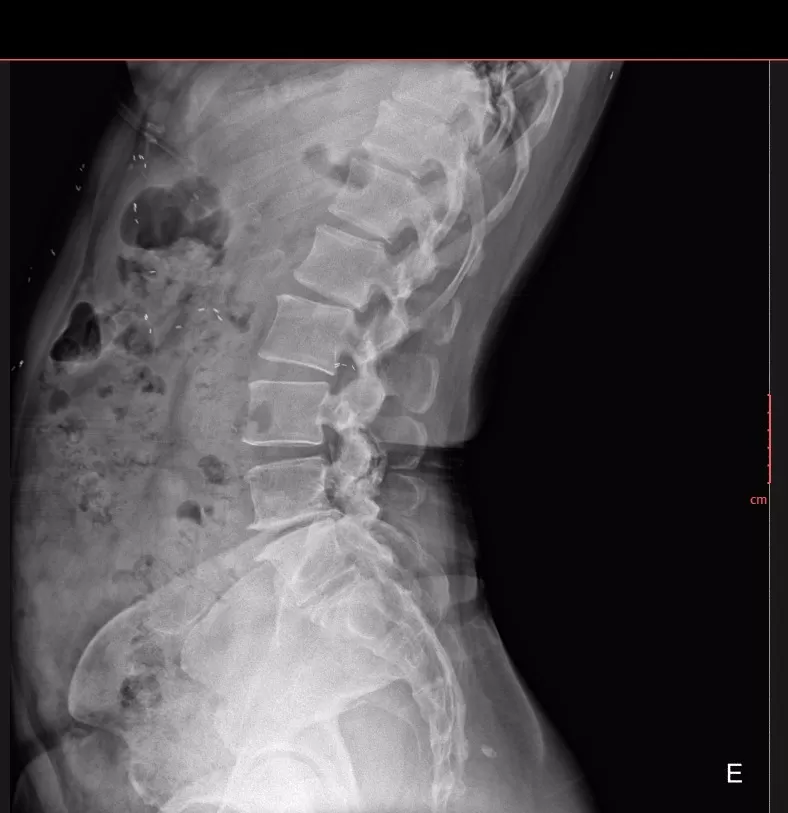

📸 Hình ảnh X-quang thường quy (đính kèm) cho thấy:

-

Nhiều nốt cản quang nhỏ, hình dạng thoi/hạt gạo,

Phân bố rải rác trong mô mềm và các khối cơ vùng ngực, bụng và thành bụng,

Các tổn thương không liên quan đến cấu trúc xương khớp.

➡️ Đây là hình ảnh điển hình gợi ý nhiễm ký sinh trùng dạng kén, đặc biệt là kén sán, một bệnh lý dễ bị chẩn đoán nhầm do triệu chứng lâm sàng không đặc hiệu.